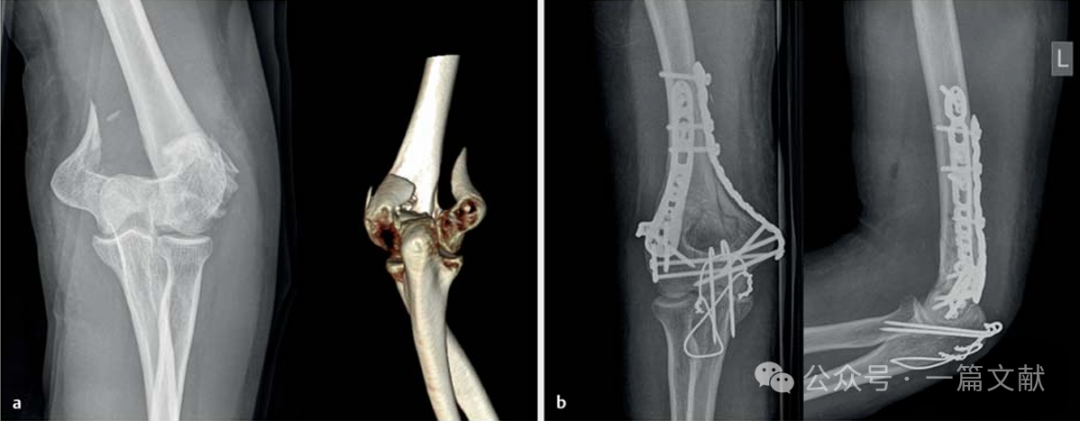

如下图:55岁患者,患有类似Monteggia损伤:左图:尺骨近端粉碎性骨折,初期采用外固定架进行固定。中图和右图:桡骨头螺钉固定,以及尺骨近端双钢板固定(背侧和尺侧LCP)。